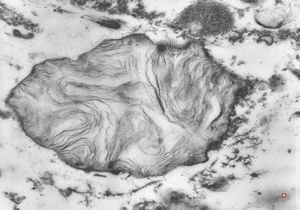

M,15y. | Wilson disease - megamitochondria